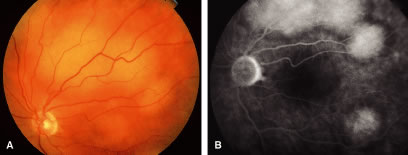

The choroid is the most common site of carcinoma metastatic to the eye (88% of eyes).6,7,10,11 Patients with choroidal metastasis usually complain of painless vision or visual field loss. About 47% of the choroidal lesions were temporal to the disc.11 Metastatic cancer to the eye was multifocal in the choroid in 28% of the eyes.11 Breast cancer was more commonly bilateral (33%) and multifocal (32%) compared with other primary neoplasms.11 There is an associated nonrhegmatogenous retinal detachment in 73% of the eyes.11 Carcinoma metastatic to the choroid is typically a placoid or dome-shaped yellow tumor of varying diameter and thickness. Multiple lesions are not infrequent (Fig. 2). The mean thickness in our series was 3 mm. Rarely a rip to the retinal pigment epithelium can develop.27 Regressed lesions are relatively flat with overlying pigment and lack of associated subretinal fluid. The differential diagnosis of choroidal metastases include amelanotic malignant melanoma, amelanotic nevus, choroidal hemangioma, choroidal osteoma, posterior scleritis, uveal effusion syndrome, Harada's disease, and central serous choroidopathy.28